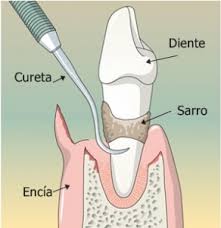

óneamente que tienen halitosis. Esta falsa sensación puede deberse a boca seca, a problemas digestivos o incluso al estrés o ansiedad. En caso de duda, el dentista te orientará sobre si sufres o no este problema y, si así fuera, cuál puede ser su solución concreta. Por si acaso, estas son algunas claves para mantener el olor de su boca a raya. pre que se acumula sarro y deben realizarse con cierta periodicidad, dependiendo de cada paciente.

pre que se acumula sarro y deben realizarse con cierta periodicidad, dependiendo de cada paciente.